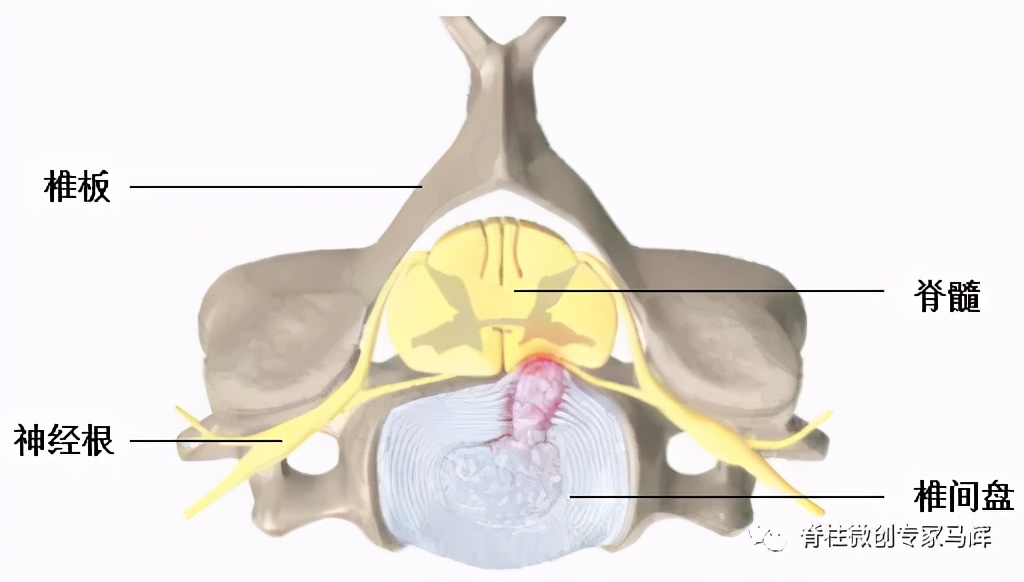

颈椎病是一种以退行性病理变化为基础,由于颈椎骨质增生,椎间盘脱出,或韧带增厚,导致颈椎脊髓、神经或血管受压,引起一系列症状的临床综合征。

颈椎微创手术创伤小、康复快,脊柱内镜可以清晰地辨别神经组织和血管等细微结构,最大限度保存了正常组织,大大降低了手术风险,特别适用于神经根型颈椎病。